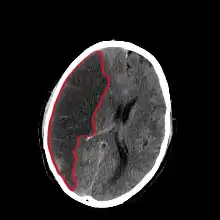

| CT scan slice of the brain showing a right-hemispheric cerebral infarct (left side of image). | |

Computed tomography (CT) and MRI scanning will show damaged area in the brain, showing that the symptoms were not caused by a tumor, subdural hematoma or other brain disorder. The blockage will also appear on the angiogram. In people who die of cerebral infarction, an autopsy of stroke may give a clue about the duration from the infarction onset until the time of death.